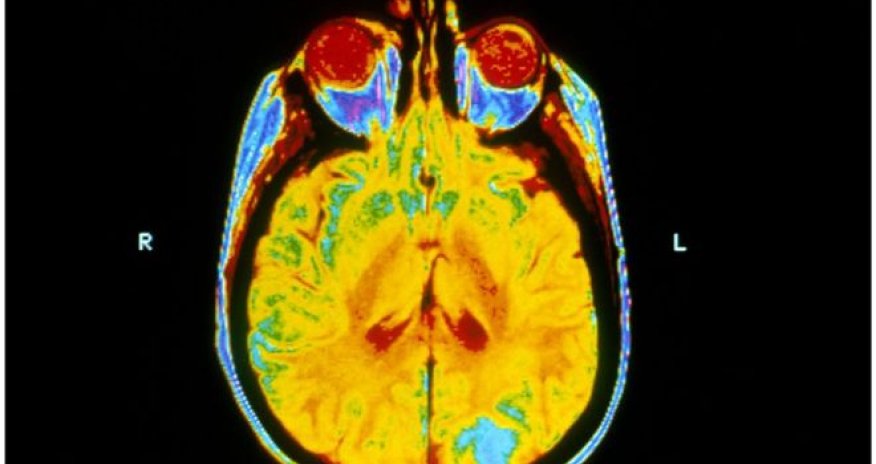

Brain radiotherapy 'no benefit' for lung cancer spread

Whole brain radiotherapy is of no benefit to people with lung cancer which has spread to the brain, says research in the Lancet.

Secondary brain tumours are usually treated with whole brain radiotherapy along with steroids and other treatments to reduce the side-effects of cancer therapies.

But it can have serious side-effects, such as nausea and extreme tiredness, and cause damage to the nervous system.